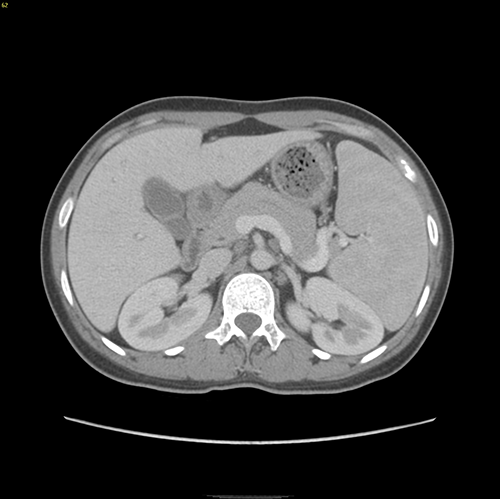

遗传性球形红细胞增多症--腹腔镜脾切除